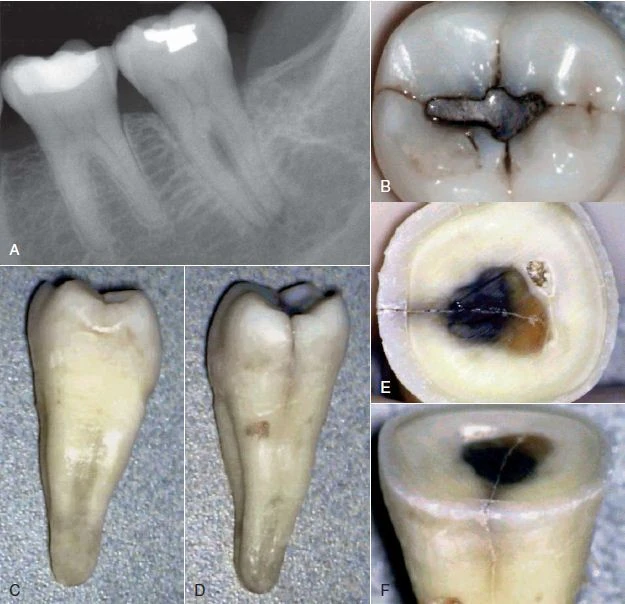

Hình 1. Phục hồi trong thân răng không khít sát có thể tạo áp lực lên răng và gây nứt dọc chân răng.

Hình 4. Thường khó chẩn đoán nứt dọc chân răng trừ khi là phải tháo bỏ miếng trám cũ

Phương pháp chiếu sáng và dùng thuốc nhuộm

Đôi khi cần phải tháo miếng trám trên răng để có thể quan sát vết nứt rõ hơn. Nhuộm bằng Xanh Methylene bằng cách bôi thuốc lên bề mặt răng bằng đầu tăm bông, thuốc nhuộm sẽ quyên qua vùng nứt và xác định vị trí đường nứt. Chiếu sáng cũng có thể hữu ích hơn bằng cách chiếu trực tiếp ánh sáng có cường độ cao vào bề mặt răng tại đường nối men – xi măng để xem mức độ lan rộng của vết nứt. Phần răng gần với nguồn sáng sẽ hấp thu ánh sáng và phát sáng, trong khi phần răng phía bên kia của vết nứt không được sánh sáng truyền qua sẽ có màu xám hơn. Mặc dù có thể phát hiện được vết nứt bằng thuốc nhuộm hoặc ánh sáng nhưng độ sâu của vết nứt không thể lúc nào cũng xác định được.

Hình 9. Đôi khi không có dấu hiệu rõ ràng cho thấy lý do răng có triệu chứng. (A) Hình ảnh X quang cho thấy răng cối lớn thứ hai hàm dưới có miếng trám sâu mức độ trung bình. (B) Thử tuỷ cho thấy răng chết tuỷ. Không chiếu sáng nên không thấy có đường nứt nào cả. (C) Chiếu ánh sáng có cường độ cao lên bề mặt răng, quan sát thấy vết nứt ở mặt ngoài. (D) Chiếu sáng vào mặt xa – trong của răng.